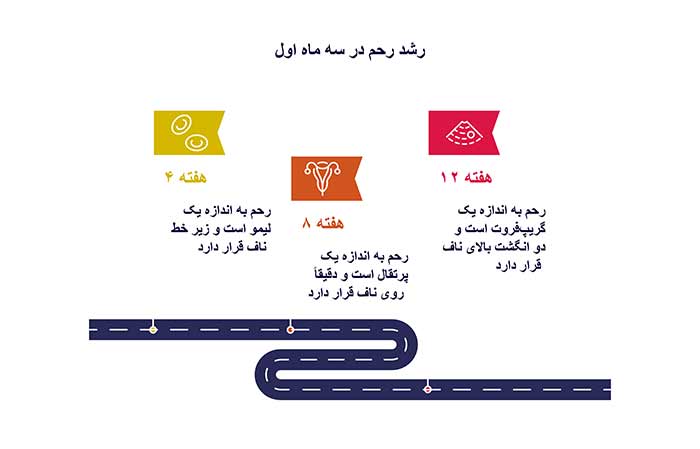

شکم در سه ماه اول به ندرست بزرگ نمیشود! رشد اصلی رحم است (از اندازه لیمو به گریپفروت). نفخ، یبوست یا چربی شکمی با رشد رحم فرق دارد.

دیاگرام رشد رحم در سه ماه اول